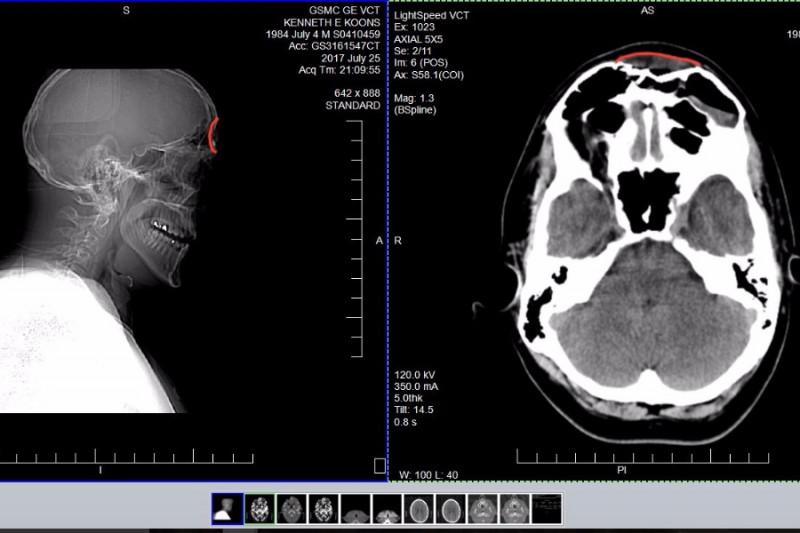

On July 25, 2017 Ken was pitching a softball game in Boulder, CO. A ball was hit back at him and hit him in the forehead. After a very long ER visit he was diagnosed with multipul Frontal Sinus Fractures. The next day we met with a facial recontruction specialist. He informed us that 97% of these types of injuries do not require surgery because the compression of the frontal sinus is only 1-2 mm. Ken's frontal sinus was compressed 8mm and will require surgery. In the next 1-2 weeks he will ungergo a tough surgery where the surgeon will open Ken's scalp with an incision going from ear to ear and use plates to correct the fractures. Ken will spend a night in the hospital but will be unable to return to work for a minimum of two weeks. If left untreated the fractures could cause more serious, life threatening damage.